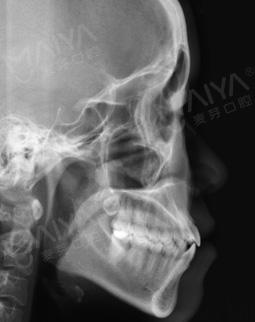

整体过程很顺利,不过医生检查的时候说有个坏牙,建议我趁早补一下,当然医生说其他的牙齿是没有问题的,不过烂牙不影响矫正,接下来流程很顺利,拍片、检查、方案都一步步的来,还有那个计算机模拟矫正方案,好先进的设备啊~~~